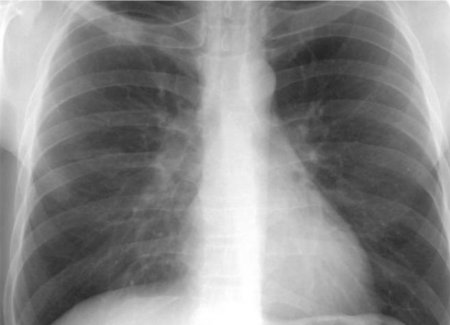

Більш агресивний перебіг, він швидше вражає більшу площу легень. Просто немає живого місця в легенях…

Якщо робити висновки по стаціонарних пацієнтах, це всі киснезалежні. Якщо в минулу хвилю були люди, які не потребували кисню (але ми їх госпіталізували, бо вони мали позитивний ПЛР-тест), то зараз це всі пацієнти, які потребують кисню. Пацієнти можуть тривало температурити, втрачати нюх (але це і тоді було). Але тут найголовніше те, що йде тотальне ураження легень. Люди всі з задишками, у них нестача повітря та потреба в кисні.